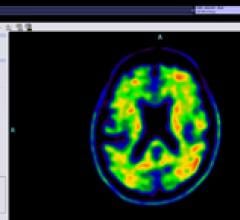

April 13, 2012 — GE Healthcare announced the preliminary results of two Phase 3 studies of its investigational positron emission tomography (PET) amyloid imaging agent, F-18 flutemetamol, where both studies met their primary endpoints.

April 11, 2012 - Siemens Healthcare is the first company worldwide to announce a complete integrated diagnostic imagingsolution proposed for the detection of amyloid plaques — one of the necessary pathological features of Alzheimer’s disease [1,2,3] — in the living brain.